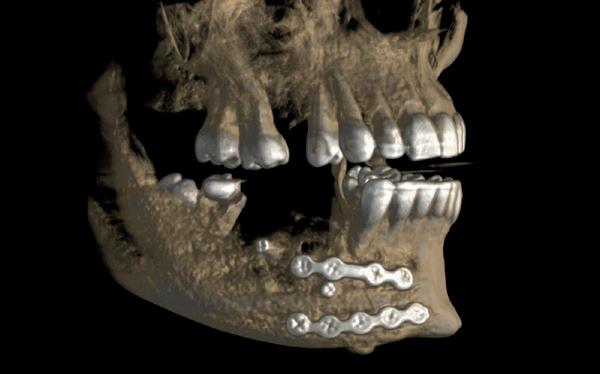

Na vier maanden wordt er een CBCT gemaakt om het botvolume te kunnen beoordelen en een digitale planning te kunnen maken voor het plaatsen van het implantaat. Tevens wordt de stabiliteit van de botpieken op het buurelementen bekeken (foto 15 en 16).

In afbeeldingen 5a-d is de implantaatkroon 37 te zien, twee jaar na plaatsing. Op de röntgenfoto is herstel van zowel corticaal als spongieus bot te zien. (De CB-CT was vervaardigd in verband met implantologische indicatie in het naastliggende gebied).